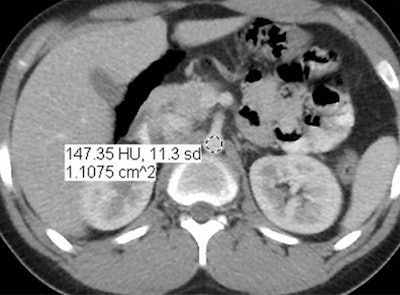

In an objective evaluation, reduced-dose MBIR images had decreased image noise compared with standard-dose 30% ASIR images (for example, 12.7 HU versus 19.4 HU in the aorta, respectively, and 8.7 HU versus 14.2 HU in the liver).